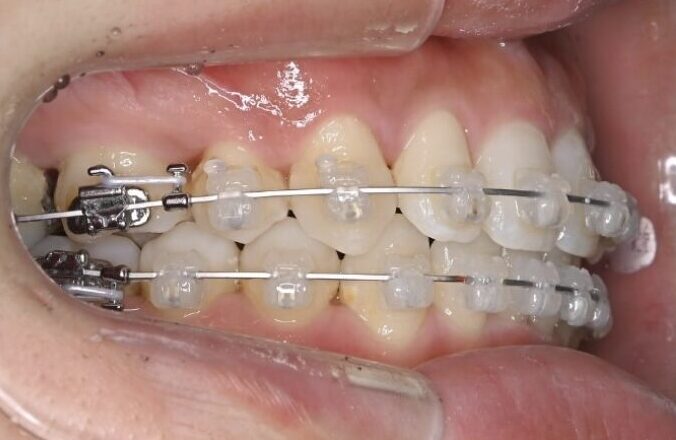

治療経過(半年後)

治療経過(1年後)

治療開始からわずか1年で、

✅ 前歯のガタガタがかなり整いました

✅ 前歯の噛み合わせも改善しました

写真で比較すると、その変化は一目瞭然です。

いかがでしょうか?

内側を向いていた上の前歯は良い角度になり、下の前歯も正常に近い見え具合となりました。抜いたところの隙間は順調に閉じ、ガタガタもなくなりました。

治療開始から半年ほどで、前歯の重なりは徐々に改善し、清掃性も向上してきました。患者さま自身も「磨きやすくなった」と実感されています。